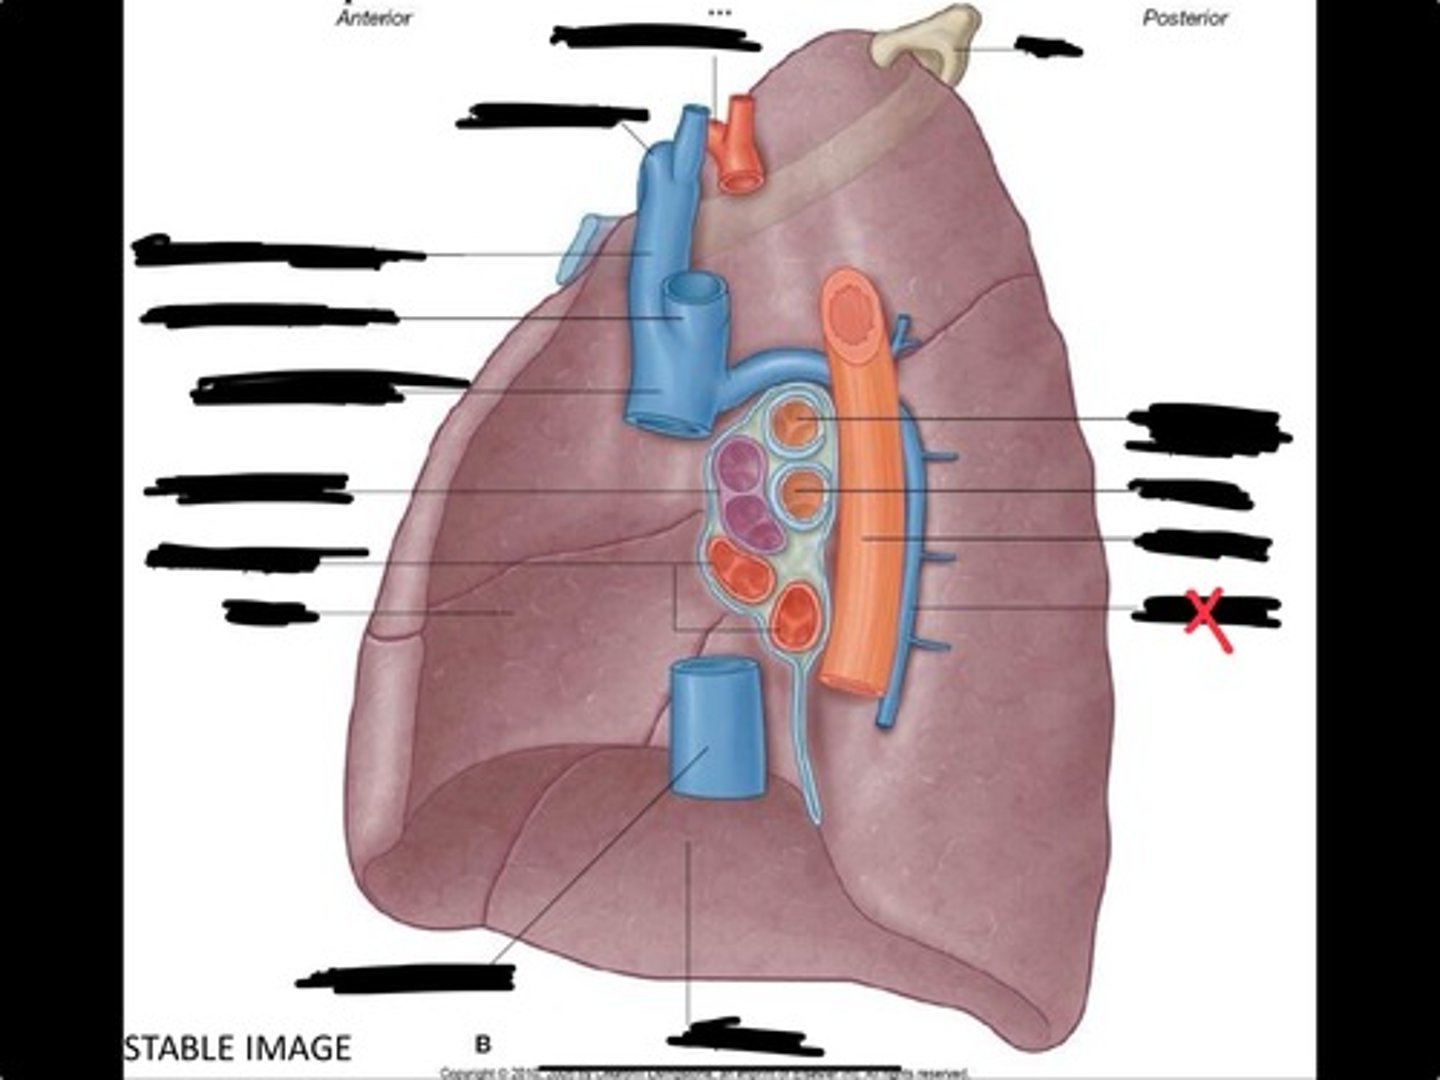

Diaphragm

Inferior vena cava

Superior vena cava

Subclavian vein

Right bracheocephalic vein

Subclavian artery

Esophagus

Bronchus

Rib 1

Left subclavian artery

Left brachiocephalic vein

Aortic arch

Pulmonary artery

Pulmonary vein

Heart

Left brachiocephalic vein

Azygos vein

Esophagus

Bronchus

Fibrous pericardium

Parietal layer of serous pericardium

Pericardial cavity

Visceral layer of serous pericardium

Junction between fibrous pericardium and adventitia

Heart

Thoracic aorta

Rib 1

Pulmonary artery

Bronchus to superior lobe